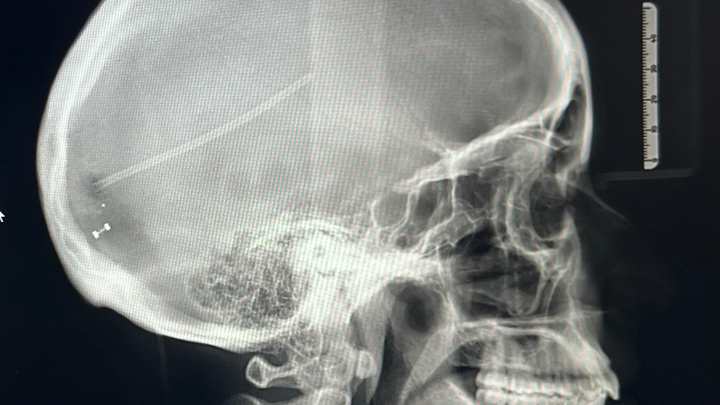

I went to Urgent Care for a CAT scan and from there, was rushed to the ICU. After MRIs, we discovered that the cerebral fluid in my brain wasn’t draining due to a pinched occipital ventricle, and the built up fluid was pushing on my eyes. This was not a problem that a lumbar puncture could fix, it required a CSF Shunt / VP Shunt. This meant that a tube would be inserted into my brain and connected to a valve attached to my skull. From there, a second tube would stretch under my skin from the valve in my skull all the way down to my stomach, acting as a drainage system for any excess fluid. So technically it was brain & abdominal surgery. People ask me when the shunt will be removed but these tools that are foreign to my body are here to stay, this isn't something that gets taken out after X amount of months. If I’m lucky, they’ll keep functioning well and future surgeries won't be necessary.